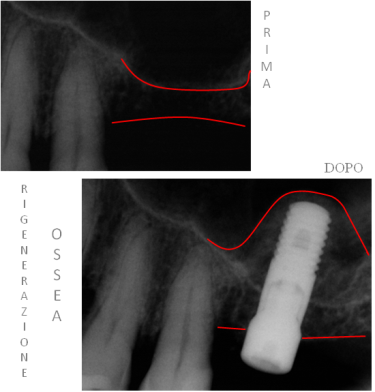

Di solito è comunque possibile. L’osso, infatti, può essere ricostruito mediante tecniche rigenerative che prevedono l’utilizzo di membrane ed innesti d’osso autologo (del paziente stesso) o di altri materiali biocompatibili; tali tecniche permettono di ottenere aumenti tridimensionali, quindi sia in termini di altezza

disponibile che di spessore. Ad esempio nell’arcata superiore la presenza del seno mascellare, una cavità posta sopra la regione molare, può in alcuni casi impedire il posizionamento di impianti. E’ possibile riempire parzialmente la cavità con un innesto osseo e procedere all’inserimento degli stessi.

Seno mascellare prominente: altezza ossea insufficiente

Dopo l’innesto osseo sonO stati inseriti gli impianti